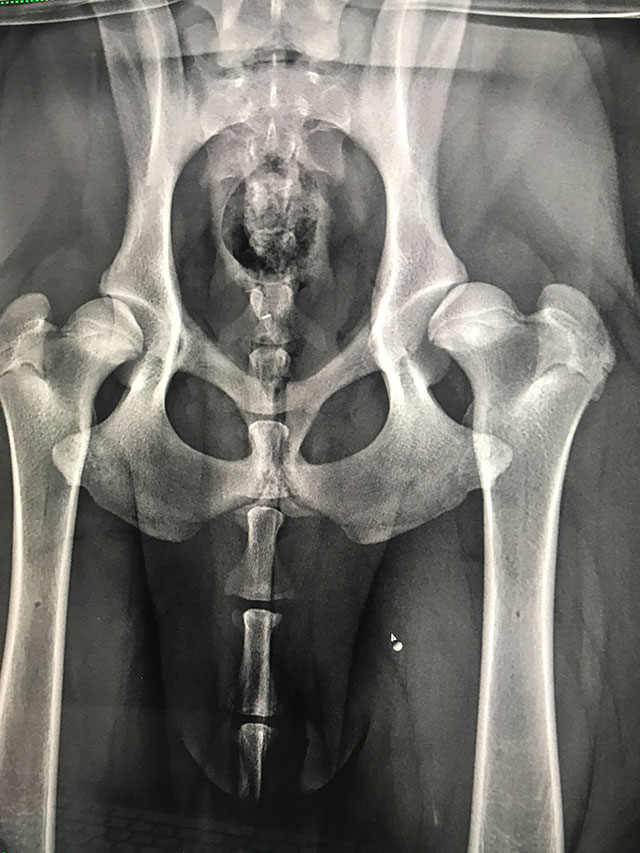

(DARthroplasty)Plastyka DAR to zabieg polegający na nadbudowie panewki stawu biodrowego z zastosowaniem autoprzeszczepu fragmentów kości pobranych najczęściej z talerza biodrowego. Operacja stanowi alternatywę dla osteotomii miednicy - zabiegu TPO/DPO - w przypadku pojawienia się zmian degeneratywnych w stawie lub zaawansowania wieku/masy pacjenta. Technika mocowania przeszczepów kostnych do krawędzi panewki stawu i ich wzajemnego ułożenia jest kluczowa dla powodzenia zabiegu.

Operacja plastyki DAR jest zabiegiem mniej agresywnym i mniej restrykcyjnym od osteotomii TPO/DPO i może być wykonywany jednocześnie na obu stawach pacjenta. Operacja DAR powinna być postrzegana jako zabieg umożliwiający funkcję stawu i ograniczający cierpienie zwierzęcia, nie jest to zabieg prowadzący do trwałego wyleczenia schorzenia o charakterze genetycznym, rozwojowym.